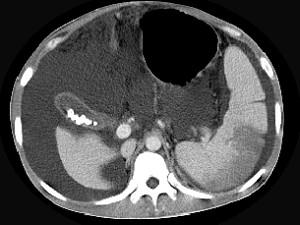

问题 患者男,29岁,乙肝病史10余年,腹胀,有移动性浊音,影像检查如图,最全面的诊断是 ( )

选项 A.肝硬化 B.肝硬化腹水 C.肝硬化腹水、脾梗、胆囊结石 D.大网膜膈下间位及脾梗 E.胆结石及脾梗

答案 C